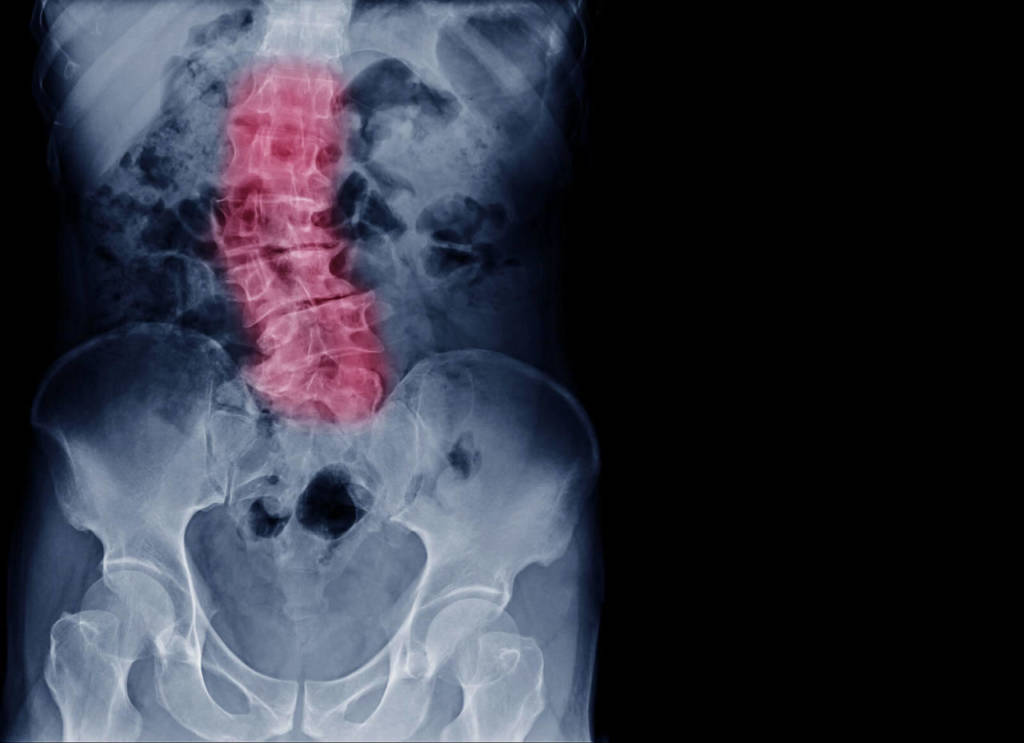

La MOC è consigliata:

- alle donne che hanno un’età superiore ai 65 anni (postmenopausa);

- agli uomini di età superiore ai 70 anni;

- alle donne che hanno avuto una perdita di statura superiore ai 6 cm;

- alle donne che presentano carenza estrogenica dovuta a menopausa precoce (registrata prima dei 45 anni), o ad amenorrea secondaria prolungata per oltre un anno, o a periodi di amenorrea premenopausale superiore a 6 mesi, oppure ipogonadismo primario;

- alle donne con anamnesi familiare materna positiva per frattura al femore, o per fratture Colles (al collo del femore), o fratture vertebrali intervenute prima dei 75 anni;

- a donne e uomini che seguono terapie con cortisonici sistemici e farmaci osteopenizzanti;

- a donne e uomini che presentano eccessiva magrezza;

- a donne e uomini che presentano malattie associate a osteoporosi;

- a donne e uomini che in precedenza hanno contratto fratture dovute a fragilità ossea;

- a donne e uomini da cui i precedenti esami radiologici hanno rilevato presenza di osteoporosi e/o cedimenti vertebrali;

- a donne e uomini che hanno avuto casi di osteoporosi in famiglia;

- a donne e uomini che presentano condizioni di rischio quali carenza di vitamina D, inadeguato introito di calcio, periodi prolungati di immobilizzazione, fumo e abuso di alcool.